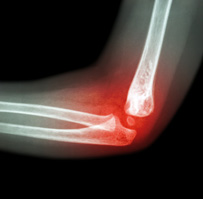

Elbow Fractures

Elbow fractures may occur from trauma, resulting from various reasons: a fall on an outstretched arm, a direct blow to the elbow or an abnormal twist to the joint beyond its functional limit.